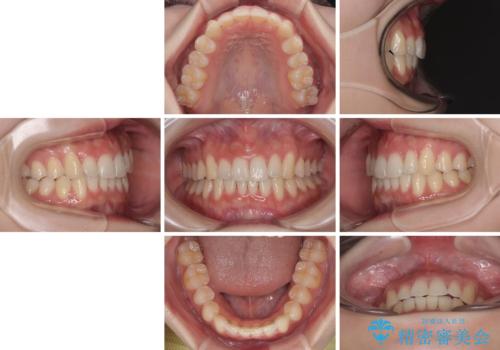

前歯が隠れるほどのデコボコをインビザライン矯正できれいに整える

- 前歯のデコボコを気にして来院された患者様です。

全体的にデコボコが多く、特に下の前歯は隠れてしまうほどの状態でした。

左右ともに奥歯の咬み合わせが理想的な位置にあったこともあり、患者様のご希望通り、インビザラインにて矯正治療を行うこととしました。

マウスピース矯正特有の、奥歯が噛みにくくなるという現象の解消に少し期間をいただきましたが、日々の装着時間を遵守していただき、綺麗な歯列に整えることができました。